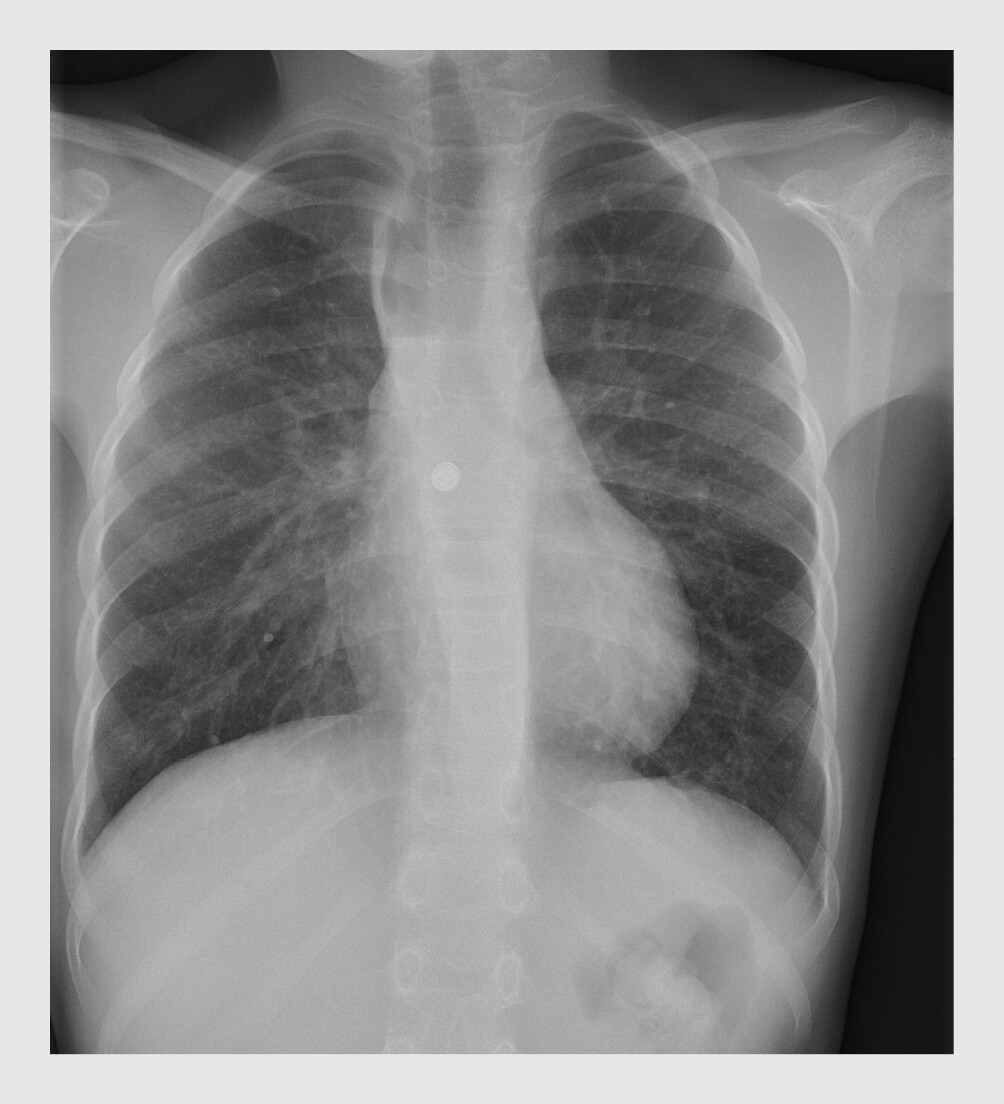

Figuur 2

Ingeslikte knoopcelbatterij

Figuur 2 | Ingeslikte knoopcelbatterij

Anterieur-posterieure röntgenfoto van de thorax van patiënt C waarop mid-oesofageaal een radio-opaak, rond voorwerp – een knoopcelbatterij – te zien. Patiënt is bekend met een type A-oesofagusatresie, waarvoor hij een reconstructie van de oesofagus heeft ondergaan met behulp van een jejunuminterponaat. Nadien is de oesofagus diverse malen gedilateerd vanwege een naadstenose. Als gevolg van die stenose is proximaal in de oesofagus een lucht-vloeistofspiegel zichtbaar.

Uit de anamnese en het lichamelijk onderzoek op de SEH kwamen geen relevante bijzonderheden naar voren, met name geen respiratoire symptomen, braken of passageklachten. Op de röntgenfoto van de thorax was mid-oesofageaal een knoopcelbatterij te zien (figuur 2). Omdat patiënt de knoopcelbatterij al enige tijd geleden (circa 10 uur) had ingeslikt en deze nabij de aorta gelegen was, werd de cardio-thoracaal chirurg verzocht om stand-by te staan. De kinderarts MDL verrichtte samen met de mdl-arts een gastroscopie. De knoopcelbatterij werd in de oesofagus aangetroffen, op 25 cm van de tandenrij (figuur 3). Na spoeling van de oesofagus kwam de knoopcelbatterij los te liggen en kon deze scopisch verwijderd worden. Omdat vervolgens bij inspectie van de slokdarmwand forse druknecrose en débris te zien waren, en mogelijk ook de muscularis mucosae, werd een maagsonde geplaatst. Vanwege het risico op mediastinitis werd patiënt behandeld met amoxicilline/clavulaanzuur en gentamicine intraveneus gedurende 7 dagen.

Op de röntgenfoto moet gelet worden op de lokalisatie van het corpus alienum en op tekenen van mogelijke complicaties, zoals vrij lucht in het mediastinum of in het peritoneum of subcutaan emfyseem. Bij een kind dat anamnestisch een magneet heeft ingeslikt (patiënt B), moet op de röntgenfoto tevens gelet worden op de aanwezigheid van meerdere magneten, omdat dit invloed heeft op het beleid. Om onderscheid te maken tussen een munt en een knoopcelbatterij, wordt op de röntgenfoto gelet op de aanwezigheid van een dubbele ring (‘halo sign’) (zie figuur 2).